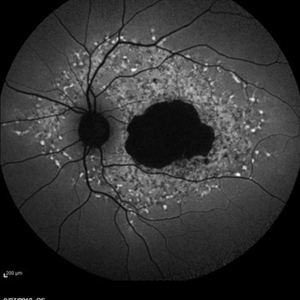

Late Stage Stargardt's Disease

Late Stage Stargardt's Disease

Mar 13 2013 by Hamid Ahmadieh, MD

Autofluorescence imaging of the left eye of a 46-year-old man with decreased VA due to advanced Stargardt's disease.

Photographer: Nayereh Hadipoor, Negah Eye Center, Tehran

Imaging device: Heidelberg Spectralis

Condition/keywords: autofluorescence imaging, Stargardt disease